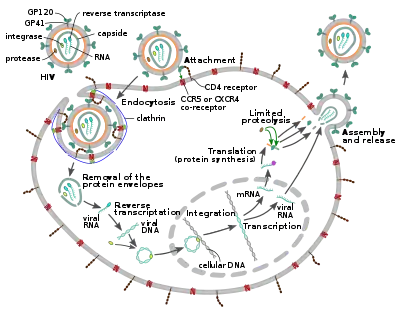

Replication cycle

Entry to the cell

The HIV virion enters macrophages and CD4+ T cells by the adsorption of glycoproteins on its surface to receptors on the target cell followed by fusion of the viral envelope with the target cell membrane and the release of the HIV capsid into the cell.[58][59]

Entry to the cell begins through interaction of the trimeric envelope complex (gp160 spike) on the HIV viral envelope and both CD4 and a chemokine co-receptor (generally either CCR5 or CXCR4, but others are known to interact) on the target cell surface.[58][59] Gp120 binds to integrin α4β7 activating LFA-1, the central integrin involved in the establishment of virological synapses, which facilitate efficient cell-to-cell spreading of HIV-1.[60] The gp160 spike contains binding domains for both CD4 and chemokine receptors.[58][59]

The first step in fusion involves the high-affinity attachment of the CD4 binding domains of gp120 to CD4. Once gp120 is bound with the CD4 protein, the envelope complex undergoes a structural change, exposing the chemokine receptor binding domains of gp120 and allowing them to interact with the target chemokine receptor.[58][59] This allows for a more stable two-pronged attachment, which allows the N-terminal fusion peptide gp41 to penetrate the cell membrane.[58][59] Repeat sequences in gp41, HR1, and HR2 then interact, causing the collapse of the extracellular portion of gp41 into a hairpin shape. This loop structure brings the virus and cell membranes close together, allowing fusion of the membranes and subsequent entry of the viral capsid.[58][59]

After HIV has bound to the target cell, the HIV RNA and various enzymes, including reverse transcriptase, integrase, ribonuclease, and protease, are injected into the cell.[58] During the microtubule-based transport to the nucleus, the viral single-strand RNA genome is transcribed into double-strand DNA, which is then integrated into a host chromosome.

HIV can infect dendritic cells (DCs) by this CD4-CCR5 route, but another route using mannose-specific C-type lectin receptors such as DC-SIGN can also be used.[61] DCs are one of the first cells encountered by the virus during sexual transmission. They are currently thought to play an important role by transmitting HIV to T cells when the virus is captured in the mucosa by DCs.[61] The presence of FEZ-1, which occurs naturally in neurons, is believed to prevent the infection of cells by HIV.[62]

HIV-1 entry, as well as entry of many other retroviruses, has long been believed to occur exclusively at the plasma membrane. More recently, however, productive infection by pH-independent, clathrin-mediated endocytosis of HIV-1 has also been reported and was recently suggested to constitute the only route of productive entry.[63][64][65][66][67]

Replication and transcription

Shortly after the viral capsid enters the cell, an enzyme called reverse transcriptase liberates the positive-sense single-stranded RNA genome from the attached viral proteins and copies it into a complementary DNA (cDNA) molecule.[68] The process of reverse transcription is extremely error-prone, and the resulting mutations may cause drug resistance or allow the virus to evade the body's immune system. The reverse transcriptase also has ribonuclease activity that degrades the viral RNA during the synthesis of cDNA, as well as DNA-dependent DNA polymerase activity that creates a sense DNA from the antisense cDNA.[69] Together, the cDNA and its complement form a double-stranded viral DNA that is then transported into the cell nucleus. The integration of the viral DNA into the host cell's genome is carried out by another viral enzyme called integrase.[68]

The integrated viral DNA may then lie dormant, in the latent stage of HIV infection.[68] To actively produce the virus, certain cellular transcription factors need to be present, the most important of which is NF-κB (nuclear factor kappa B), which is upregulated when T cells become activated.[70] This means that those cells most likely to be targeted, entered and subsequently killed by HIV are those actively fighting infection.

Assembly and release

The final step of the viral cycle, assembly of new HIV-1 virions, begins at the plasma membrane of the host cell. The Env polyprotein (gp160) goes through the endoplasmic reticulum and is transported to the Golgi apparatus where it is cleaved by furin resulting in the two HIV envelope glycoproteins, gp41 and gp120.[87] These are transported to the plasma membrane of the host cell where gp41 anchors gp120 to the membrane of the infected cell. The Gag (p55) and Gag-Pol (p160) polyproteins also associate with the inner surface of the plasma membrane along with the HIV genomic RNA as the forming virion begins to bud from the host cell. The budded virion is still immature as the gag polyproteins still need to be cleaved into the actual matrix, capsid and nucleocapsid proteins. This cleavage is mediated by the packaged viral protease and can be inhibited by antiretroviral drugs of the protease inhibitor class. The various structural components then assemble to produce a mature HIV virion.[88] Only mature virions are then able to infect another cell.

Spread within the body

The classical process of infection of a cell by a virion can be called "cell-free spread" to distinguish it from a more recently recognized process called "cell-to-cell spread".[89] In cell-free spread (see figure), virus particles bud from an infected T cell, enter the blood or extracellular fluid and then infect another T cell following a chance encounter.[89] HIV can also disseminate by direct transmission from one cell to another by a process of cell-to-cell spread, for which two pathways have been described. Firstly, an infected T cell can transmit virus directly to a target T cell via a virological synapse.[60][90] Secondly, an antigen-presenting cell (APC), such as a macrophage or dendritic cell, can transmit HIV to T cells by a process that either involves productive infection (in the case of macrophages) or capture and transfer of virions in trans (in the case of dendritic cells).[91] Whichever pathway is used, infection by cell-to-cell transfer is reported to be much more efficient than cell-free virus spread.[92] A number of factors contribute to this increased efficiency, including polarised virus budding towards the site of cell-to-cell contact, close apposition of cells, which minimizes fluid-phase diffusion of virions, and clustering of HIV entry receptors on the target cell towards the contact zone.[90] Cell-to-cell spread is thought to be particularly important in lymphoid tissues, where CD4+ T cells are densely packed and likely to interact frequently.[89] Intravital imaging studies have supported the concept of the HIV virological synapse in vivo.[93] The many dissemination mechanisms available to HIV contribute to the virus' ongoing replication in spite of anti-retroviral therapies.[89][94]